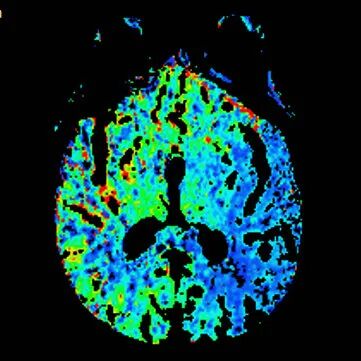

查体BP 160/89mmHg,清醒,双眼左侧凝视位、不可纠正,混合性失语,右侧中枢性面舌瘫,右侧肢体肌力0级,右侧病理征阳性。NIHSS评分18分。随机血糖4.8mmol/L。心电图:正常。颅脑CT无出血及新发梗死灶,多模态CT示左侧大脑中动脉闭塞、左侧大脑半球低灌注。

多模态CT。